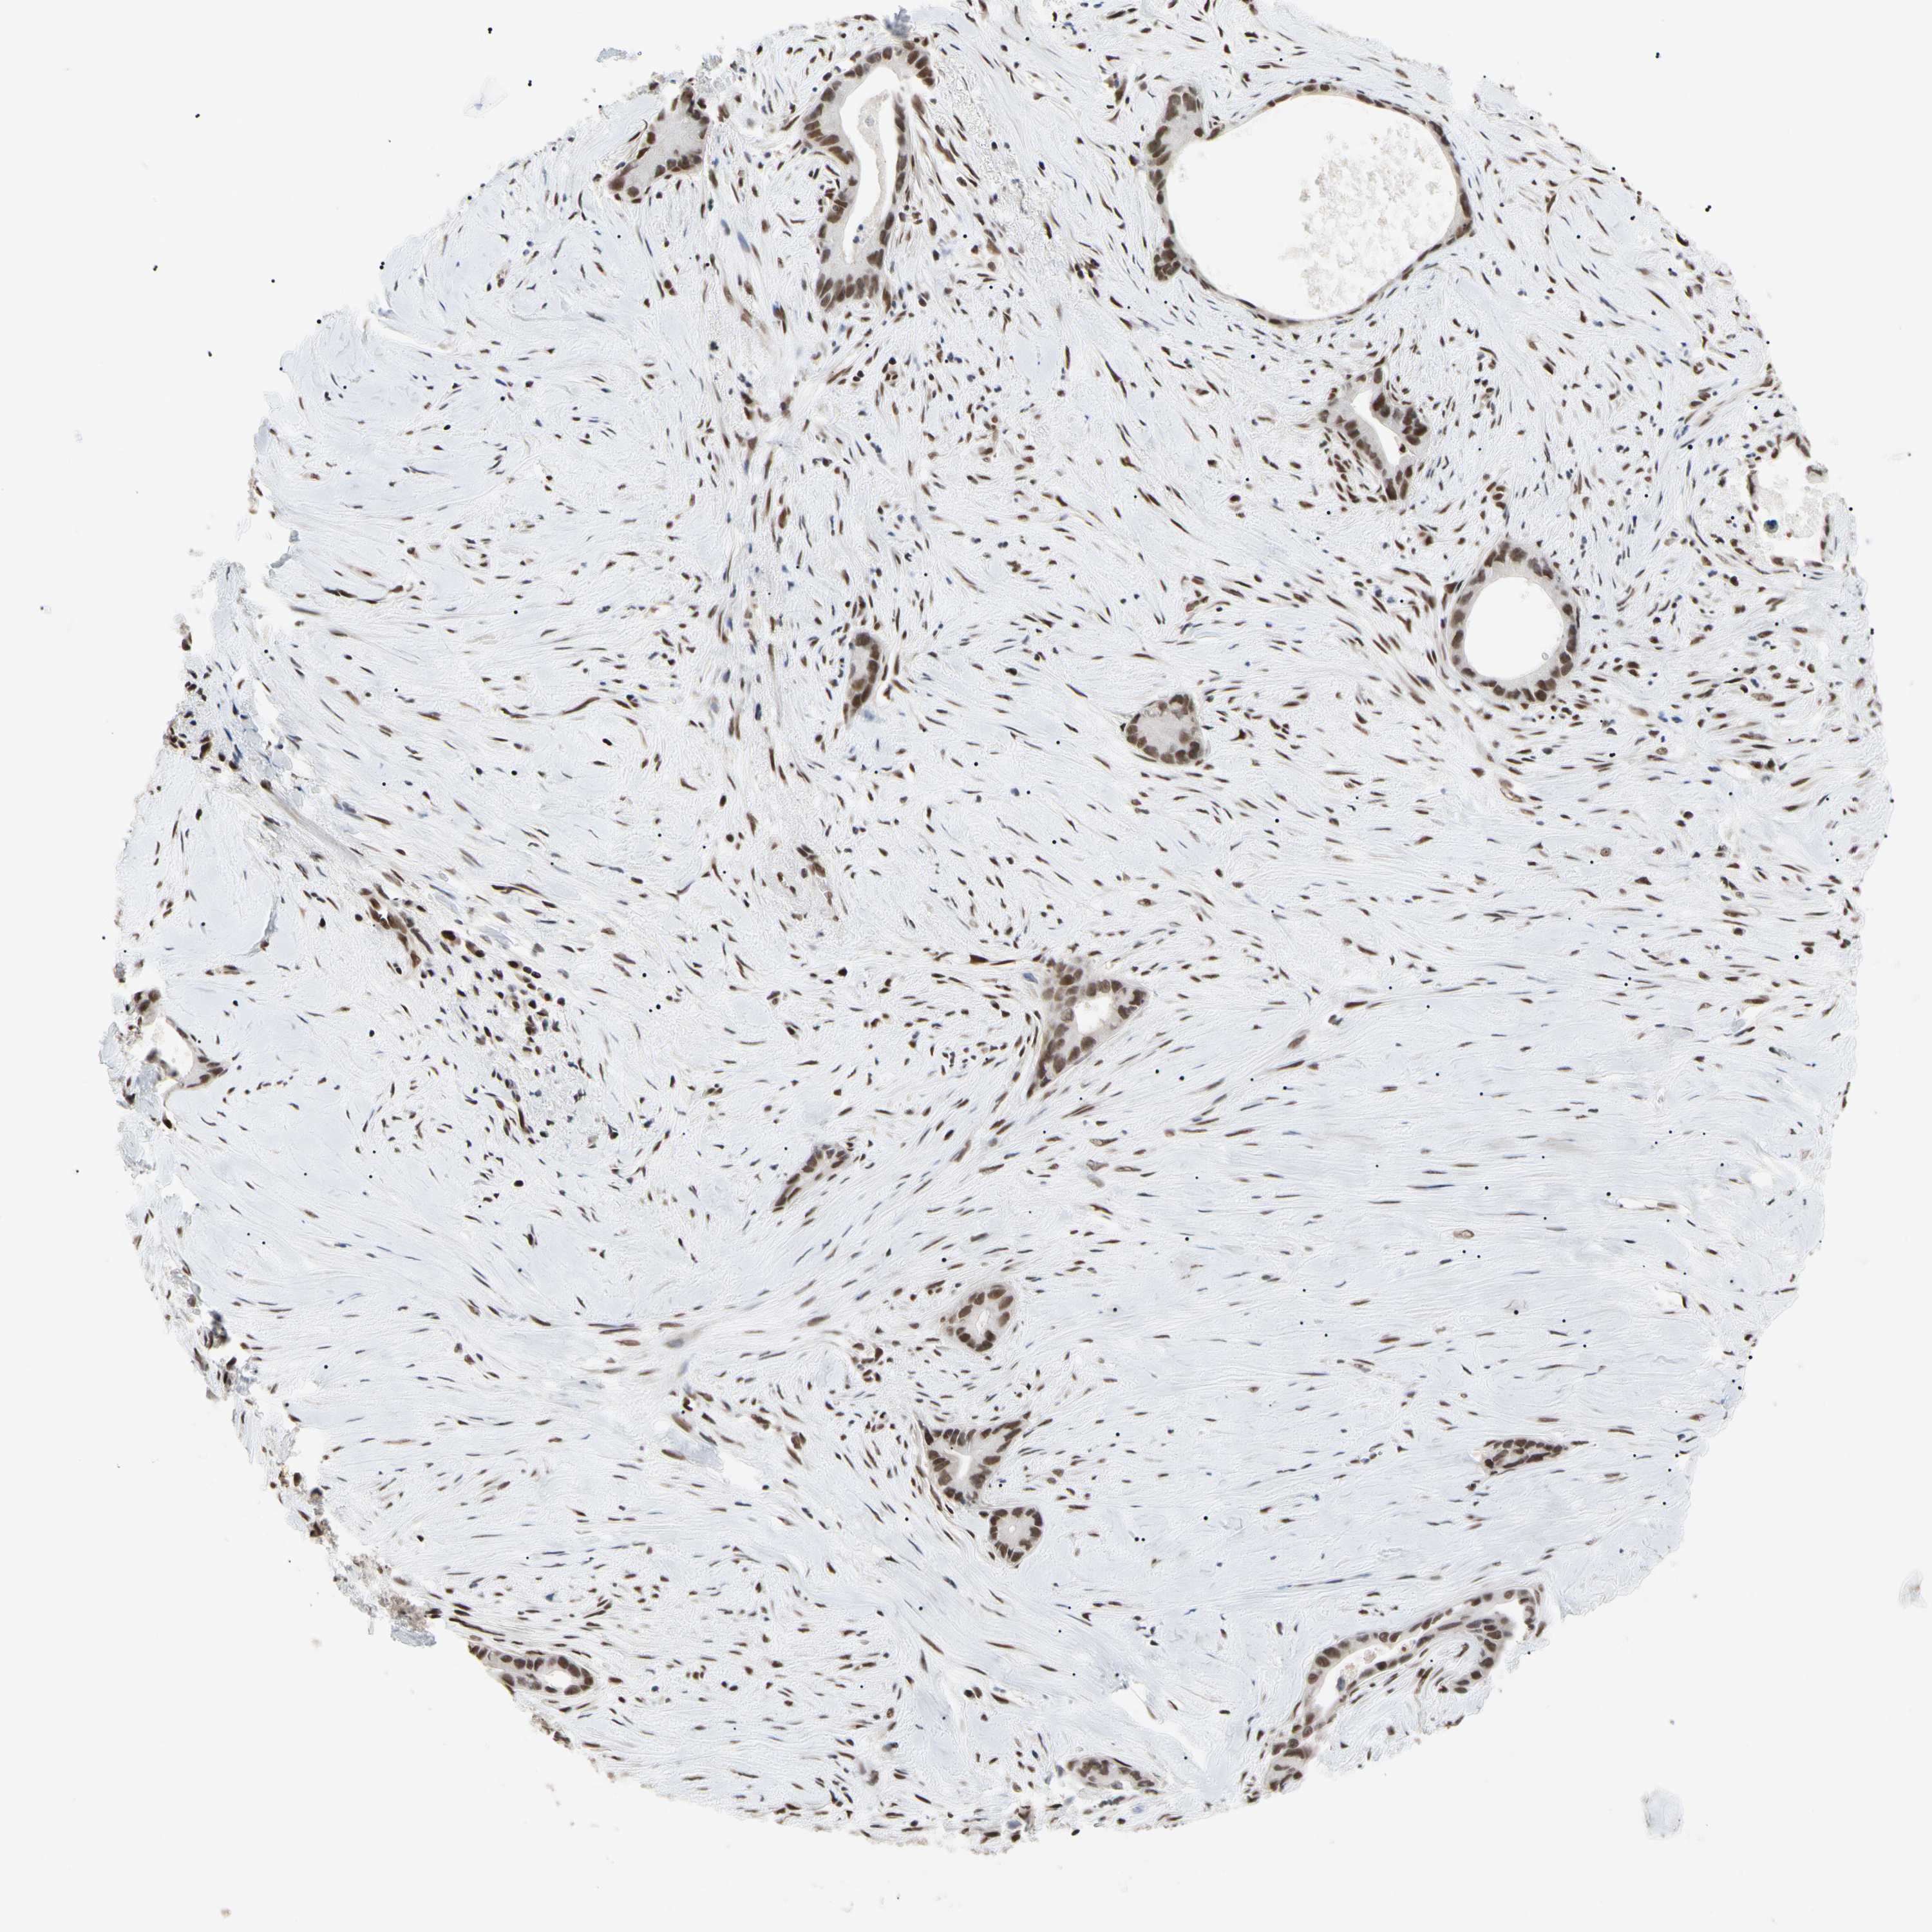

LIVER CANCER - Protein expressioni

A mouse-over function shows sample information and annotation data. Click on an image to view it in a full screen mode. Samples can be filtered based on level of antibody staining by selecting one or several of the following categories: high, medium, low and not detected. The assay and annotation is described here.

Note that samples used for immunohistochemistry by the Human Protein Atlas do not correspond to samples in the TCGA dataset.

Antibody stainingi

Antibody staining in the annotated cell types in the current human tissue is reported as not detected, low, medium, or high, based on conventional immunohistochemistry profiling in selected tissues. This score is based on the combination of the staining intensity and fraction of stained cells.

Each image is clickable and will lead to virtual microscopy that enables deeper exploration of all samples and also displays staining intensity scores, fraction scores and subcellular localization as well as patient and tissue information for each sample.

Antibody HPA008320

Antibody HPA008502

Staining

High

Medium

Low

Not detected

Intensity

Strong

Moderate

Weak

Negative

Quantity

>75%

75%-25%

<25%

None

Location

Nuclear

Cytoplasmic/membranous

Cytoplasmic/membranous,nuclear

Cholangiocarcinoma

Carcinoma, Hepatocellular, NOS